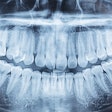

Dental x-rays cause a lot more cancer than previously assumed, according to new estimates published in the September Journal of the American Dental Association (September 2008, Vol. 139:9, pp. 1237-1243).

"The dental radiographic procedures we evaluated in this study are 32% to 422% riskier than previously thought," concluded researchers from the University of North Carolina (UNC) at Chapel Hill and the University of California, Los Angeles.

The results? Dental patients, according to this study, are receiving between 0.32 and 4.22 times more radiation than previously estimated. The dose ranged tremendously from one procedure to the next: a bitewing with F-speed film and rectangular collimation exposed the patient to an effective dose (the weighted sum of all organs exposed) of 5 microsieverts (µSv). By contrast, a full-mouth series with D-speed film and round collimation exposed the patient to 388 µSv.

Dr. Ludlow and his colleagues used a risk coefficient of 0.055 cancer events per sievert to calculate how much harm dental radiation causes. They determined that the risk of fatal cancer ranged from 0.3 in a million for a lateral cephalometric x-ray, to 21 in a million for a full-mouth series with D-speed film and round collimation.

The finding reinforces ADA recommendations (JADA, September 2006, Vol. 137:9, pp. 1304-1312) that dentists should use F-speed film and rectangular collimation, and take x-rays more sparingly, the investigators wrote. The combination of the fast film and rectangular collimation cuts patients' radiation exposure by a factor of 10, they noted.